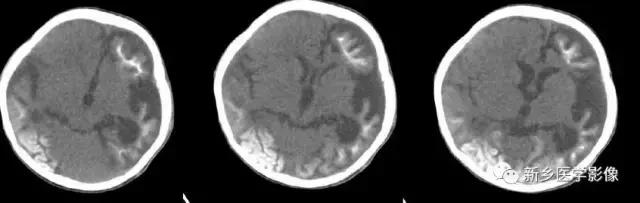

6.脑室周围白质软化症

主要与缺血缺氧及感染有关。

常见于早产儿。常见于早产儿的原因与胚胎期脑部损害发生的时间有关,胚胎早中期脑损害主要引发发育畸形,晚期主要引起脑血管改变。

由于脑室周围白质的血供分别来自脑室区和远脑室区的终动脉,未成熟儿终动脉深穿支的侧支循环尚未建立,而胚胎晚期脑室周围白质对缺血缺氧敏感。所以,脑室周围白质软化症多见于早产儿。

由于侧脑室周围有软化萎缩,故扩大的侧脑室外缘常不规则,不光整,这种不规则、不光整是本病引起脑室扩大的特征,另外,本病均表现有脑白质量减少及脑白质内斑片状软化病灶,脑白质减少严重时表现为部分区域白质消失,脑皮层与脑室侧缘接近甚至相连。CT表现为斑片状低密度灶。MR T1WI上呈低信号,T2WI呈高信号。